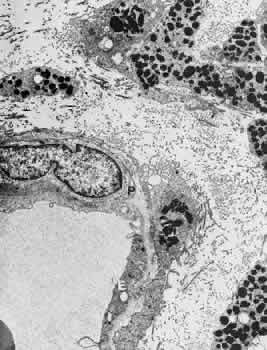

Venules are usually less than 20 μm in diameter.15 The media is composed of a single layer of cells resembling pericytes, containing poorly developed myofilaments and dense bodies. Elastin is not present. The adventitia contains little other than the basement membrane surrounding the pericyte (Fig. 5).

Fig. 5. Electron micrograph of a human retinal venule. E, endothelial cell. The pericyte (P) contains abundant mitochondria and rough-surfaced endoplasmic reticulum. Pinocytotic vesicles are present, and the myofilaments are poorly developed.